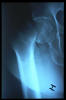

Fractura cuello fémur. Prótesis completa.

Fractura intertrocantérea de fémur, osteosíntesis

Fractura de cuello de fémur.

Fractura de fémur, osteosíntesis

Fractura de fémur, prótesis parcial de cadera

osteosíntesis fractura fémur

Fractura de cuello de fémur

Fractura de cuello de fémur con tornillos de tracción